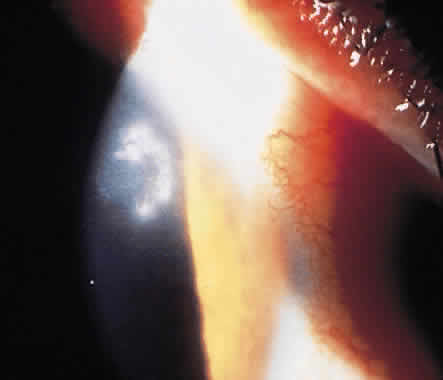

The clinical onset of B. anthracis keratitis can begin with multifocal epithelial opacities that lead to a focal stromal infiltrate. B. cereus keratitis also can be extremely severe and can rapidly progress to perforation. It may be characterized by a ring infiltrate in the stroma that is remote from the site of the injury (Fig. 1).11 A history of a corneal foreign body or other corneal trauma preceding the infection generally can be obtained (Fig. 2). B. cereus is one of the most destructive organisms affecting the inner eye that often follows trauma. The source of the organisms can be either soil contamination of the object penetrating the eye or direct inoculation of organisms colonizing the eye surface. B. cereus panophthalmitis almost always ends in complete loss of light perception within 48 hours of the injury with massive vitreoretinal destruction. The pathogenesis of B. cereus panophthalmitis is incompletely defined. At least three toxins have been implicated: necrotic toxin (a heat-labile enterotoxin), cereolysin (a potent hemolysin named after the species), and phospholipase C (a potent lecithinase). It is likely that the rapid destruction of the eye, which is characteristic of B. cereus infection, is the result of interactions of these toxins and unidentified factors.

Fig. 1. Necrotizing ring infiltrate caused by Bacillus cereus.